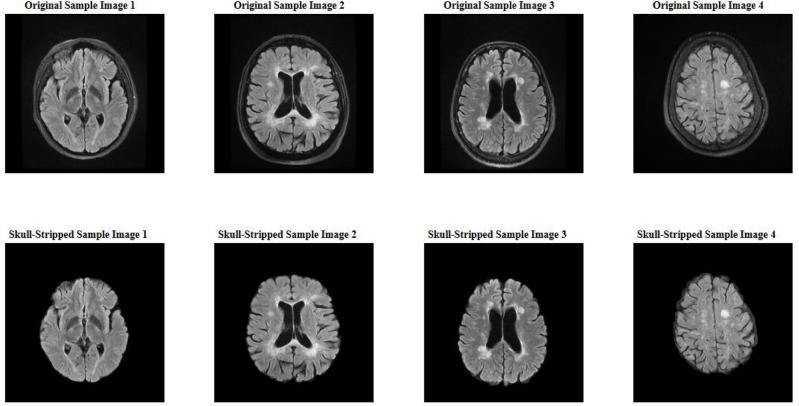

This study presents an automated system using Convolutional Neural Networks (CNNs) for segmenting FLAIR Magnetic Resonance Imaging (MRI) images to aid in the diagnosis of Multiple Sclerosis (MS). The dataset included 103 patients from Imam Khomeini Hospital, Tehran and an additional 10 patients from an external center. Key preprocessing steps included skull stripping, normalization, resizing, segmentation mask processing, entropy-based exclusion, and data augmentation. The nnU-Net architecture tailored for 2D slices was employed and trained using a fivefold cross-validation approach. In the slice-level classification approach, the model achieved 83% accuracy, 100% sensitivity, 75% positive predictive value (PPV), and 99% negative predictive value (NPV) on the internal test set. For the external test set, the accuracy was 76%, sensitivity 100%, PPV 68%, and NPV 100%. Voxel-level segmentation showed a Dice Similarity Coefficient (DSC) of 70% for the internal set and 75% for the external set. The CNN-based system with nnU-Net architecture demonstrated high accuracy and reliability in segmenting MS lesions, highlighting its potential for enhancing clinical decision-making.

本研究提出了一个使用卷积神经网络(cnn)分割FLAIR磁共振成像(MRI)图像的自动化系统,以帮助诊断多发性硬化症(MS)。该数据集包括来自德黑兰伊玛目霍梅尼医院的103名患者和来自外部中心的另外10名患者。关键的预处理步骤包括颅骨剥离、归一化、调整大小、分割掩码处理、基于熵的排除和数据增强。采用为2D切片定制的nnU-Net架构,并使用五倍交叉验证方法进行训练。在切片级分类方法中,模型在内部测试集上的准确率为83%,灵敏度为100%,阳性预测值(PPV)为75%,阴性预测值(NPV)为99%。对于外部测试集,准确度为76%,灵敏度为100%,PPV为68%,NPV为100%。体素级分割显示,内部集的Dice Similarity Coefficient (DSC)为70%,外部集为75%。采用nnU-Net架构的基于cnn的系统在MS病变分割方面显示出较高的准确性和可靠性,突出了其增强临床决策的潜力。